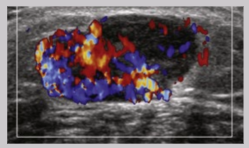

Tendinitis

Tendon-related pain and symptoms associated with inflammation → increased vascularity

Tenosynovitis

Inflammation of sheath surrounding tendon → presents as fluid accumulation around tendon